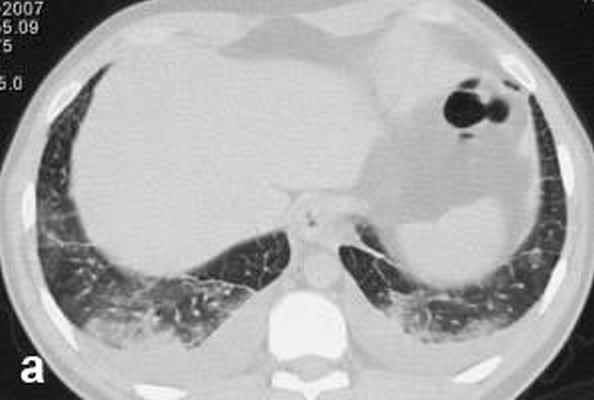

Больной С., 33 г., по профессии электромонтажник, поступил в НМХЦ им. Н.И. Пирогова 5 февраля 2007 г. с жалобами на одышку при незначительной физической нагрузке, кашель с трудноотделяемой мокротой слизистого характера, общую слабость, похудание на 10 кг, субфебрильную температуру тела. С 2000 г. у пациента диагностировали хронический ринит, синусит, полипоз носа. Для купирования затрудненного носового дыхания последние 3 года применял кортикостероидный назальный спрей. В связи с возникновением приступов удушья 2006 г. в НИИ аллергологии и иммунологии диагностирована бронхиальная астма среднетяжелого течения. Назначена терапия симбикортом с положительным эффектом. Ухудшение состояния с декабря 2006, когда появились субфебрильная температура тела, приступы затрудненного дыхания, одышка при физической нагрузке, снижение аппетита. При КТ органов грудной клетки, выполненной амбулаторно 25.01.07г.: лимфаденопатия средостения (лимфоузлы до 2-2,5 см) с образованием конгломерата размером 38 х 40 х 50 мм (рис. 1), снижение прозрачности легочной ткани по типу «матового стекла» (рис. 2а), диффузное уплотнение интерстициальной ткани (рис. 2б), двусторонний гидроторакс. Заподозрена опухоль переднего средостения в связи, с чем пациент госпитализирован для морфологической верификации диагноза.

| Рис. 1. КТ грудной клетки: а - в области вилочковой железы образование размером 38х40х50мм, б - увеличение лимфатических узлов средостения до 20-25 мм. | |

| Рис. 2. КТ грудной клетки: а - снижение прозрачности по типу “матового стекла“, б - диффузное уплотнение интерстициальной ткани. | |